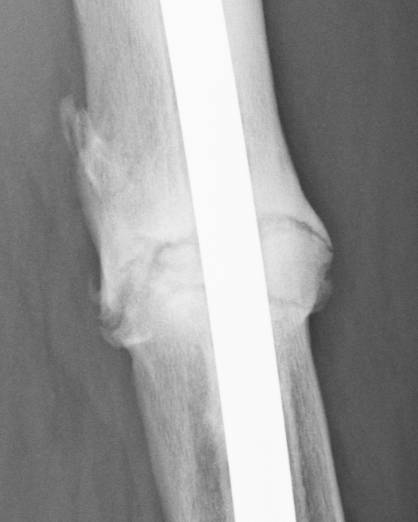

June 22, 2010 X-ray update

Forive me people for I have sinned. It has been two years since my last update. But seriously, there is much improvement to report. Based on activity and how it feels things are progressing very well. The x-rays also show more bone growth which adds to the good sign.

Feb. 21, 2008 June 22, 2010